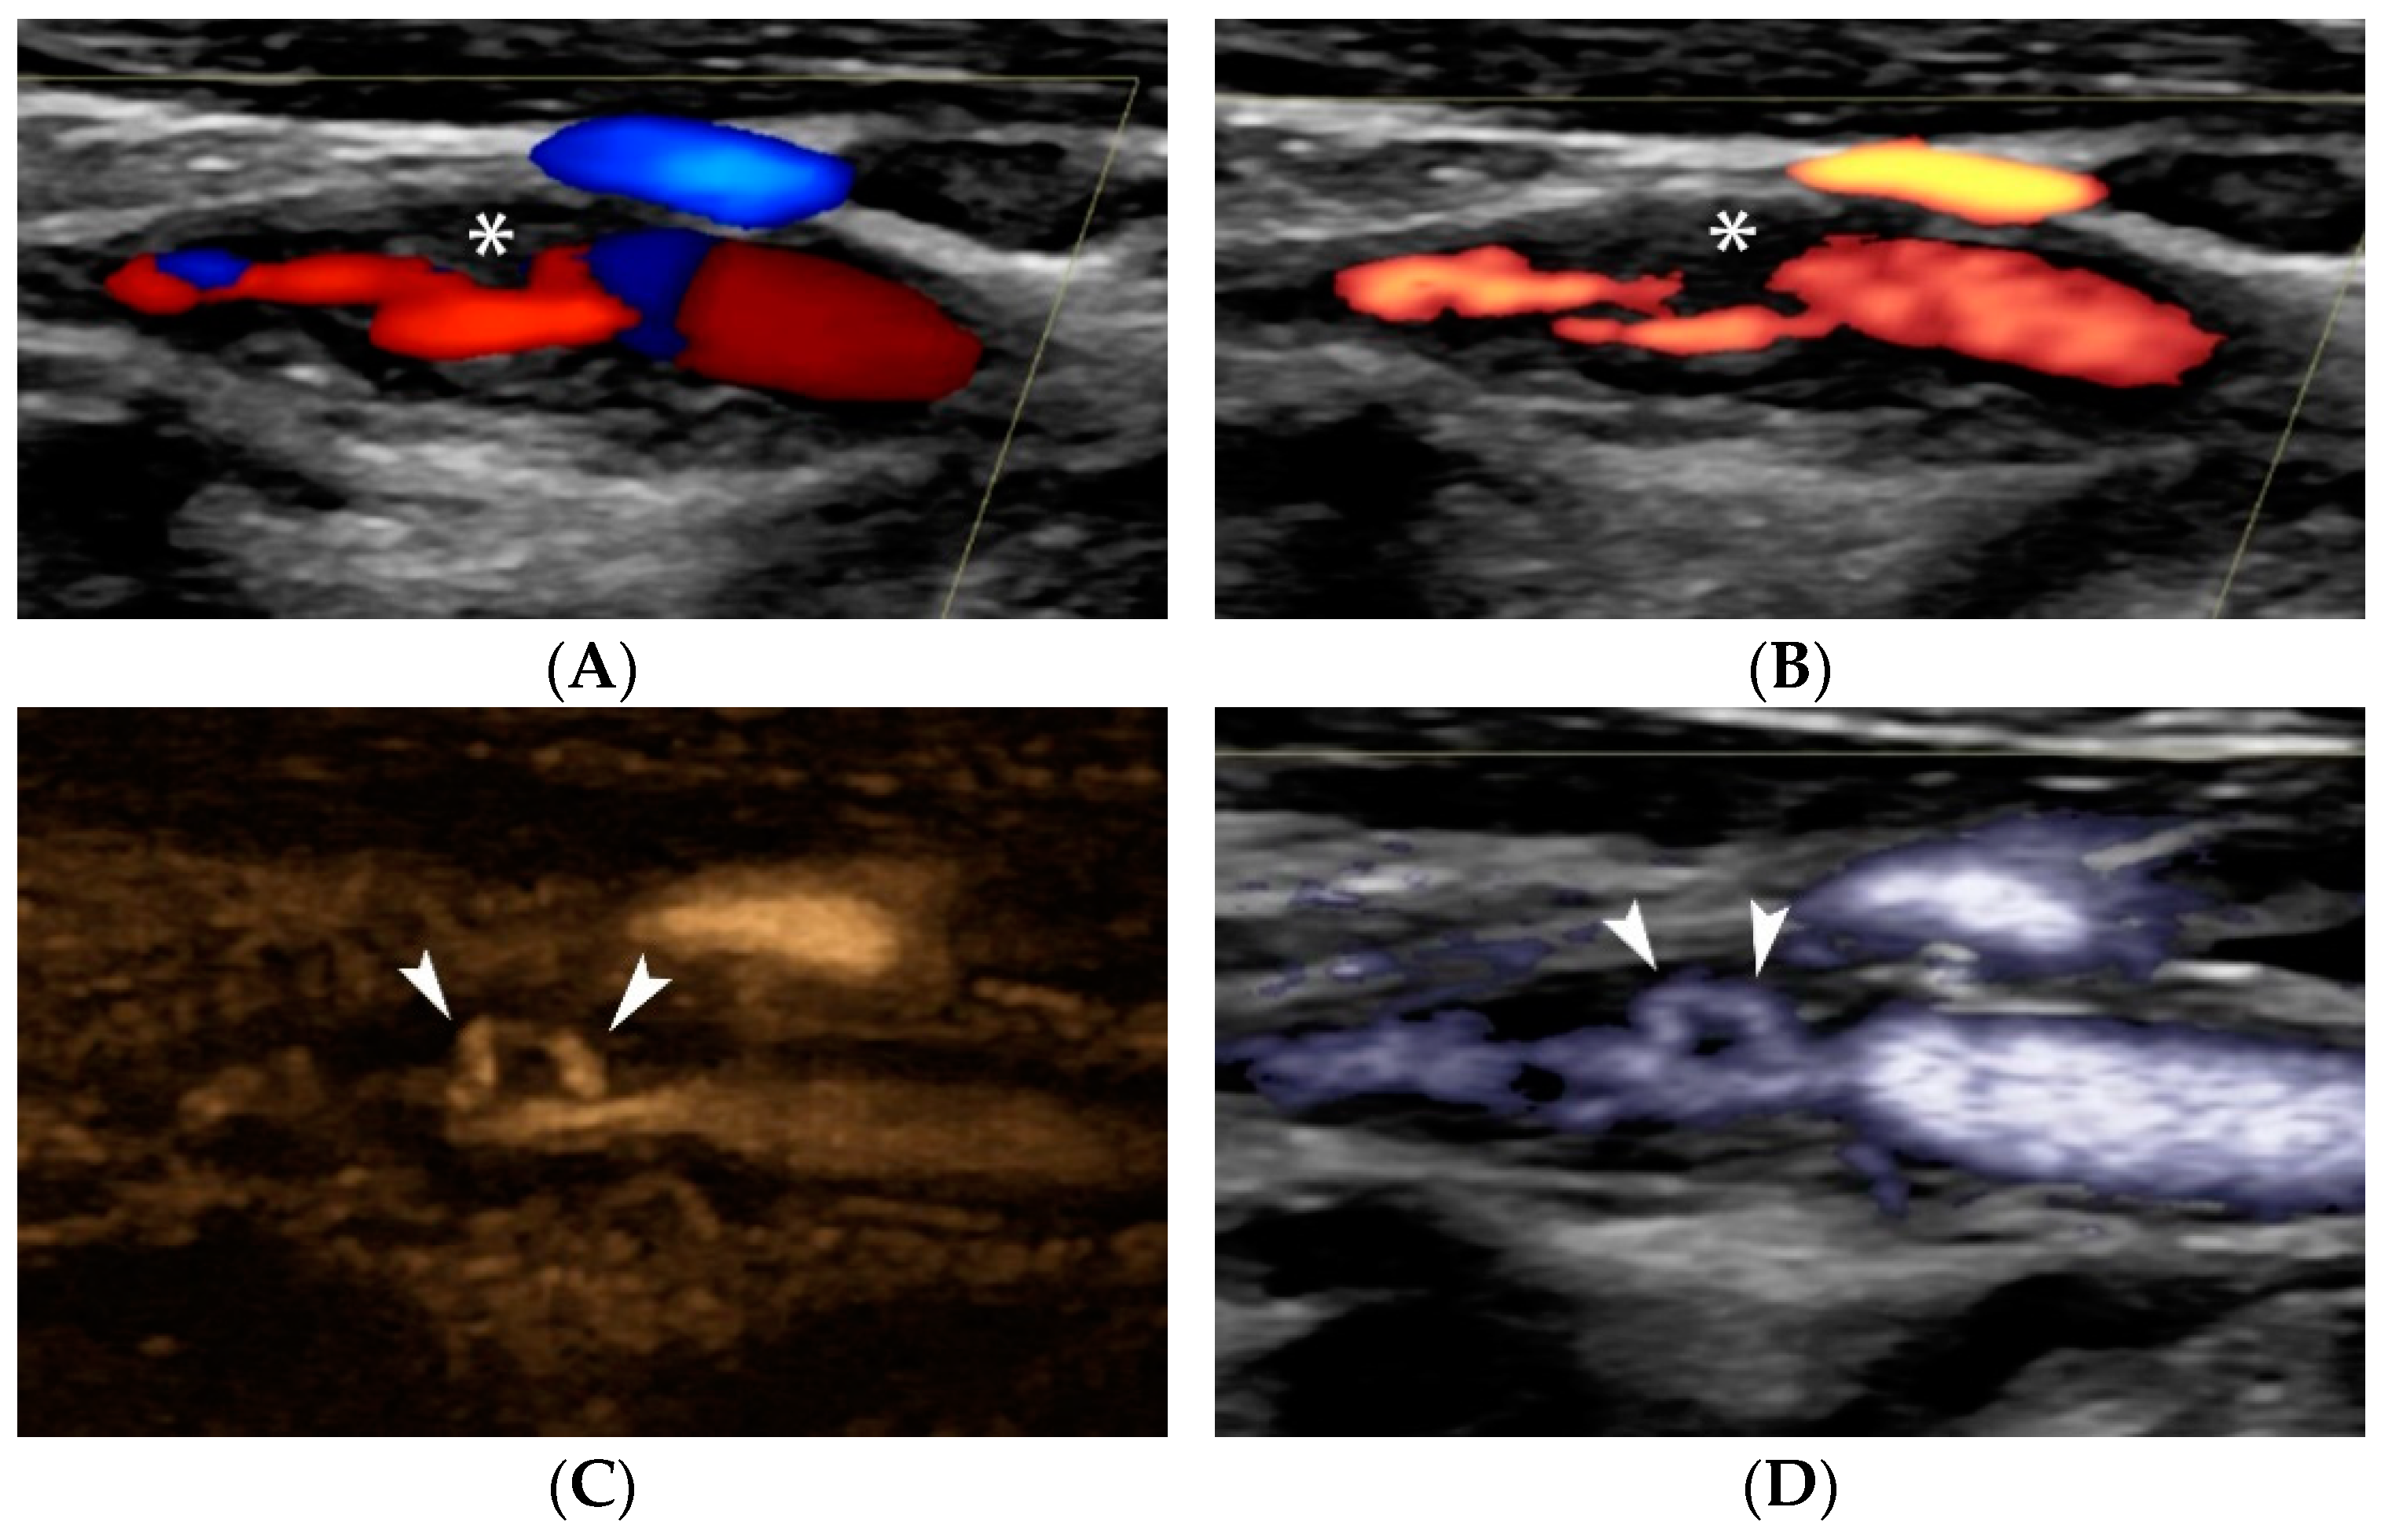

4.1.4. Plaque Ulceration

3. Surface Morphology